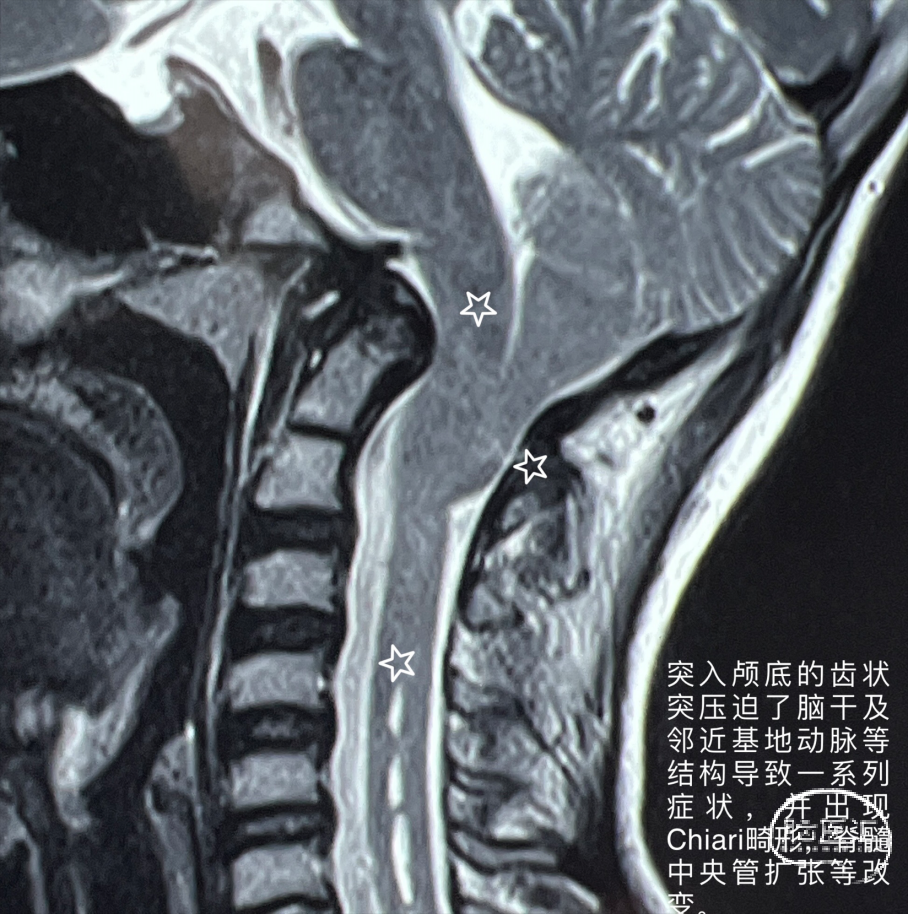

颅底凹陷症(basilarinvagination)的主要发病原因为先天性⻣质发育不良所致,由于在胚胎发⽣学上神经管在寰枕部闭合最晚所以先天性畸形容易发⽣在此区。少数可继发于其他疾病。本病分为2型:① 先天型:⼜称原发性颅底凹陷症,伴有寰枕融合、枕⻣变扁、枕⻣⼤孔变形、⻮状突向上移位甚⾄进 ⼊枕⻣⼤孔内,致使枕⻣⼤孔前后径缩⼩。在胚胎发育2~3周时由于胚胎分节的局部缺陷,寰椎不同程度地进⼊枕⻣⼤孔内有时与之融合等。近年来有⼈发现本病与遗传因素有关,即同⼀家族兄弟姐妹中可有数⼈发病。②继发型:⼜称获得型颅底凹陷症,较少⻅常继发于⻣炎、成⻣不全佝偻病⻣软化症、类⻛湿性关节炎或甲状旁腺功能亢进等导致颅底⻣质变软,变软的颅底⻣质受到颈椎压迫⽽内陷枕⼤孔升⾼,有时可达岩⻣尖,且变为漏⽃状。同时颈椎也套⼊颅底,为了适应寰椎后⼸,在枕⼤孔后⽅可能出现隐窝,⽽寰椎后⼸并不与枕⻣相融合。颅底凹陷症导致枕⻣⼤孔狭窄,后颅窝变⼩,压迫延髓、⼩脑及牵拉神经根产⽣⼀系列症状,合并有椎动脉受压出现供⾎不⾜表现。晚期常出现脑脊液循环障碍⽽导致梗阻性脑积⽔和颅内压增⾼。颅底凹陷常合并脑脊髓和其他软组织畸形,如⼩脑扁桃体疝、脊髓空洞症及蛛⽹膜粘连等。呼吸肌功能衰减常常使患者感觉⽓短,说话⽆⼒,严重者可能出现不同程度的中枢性呼吸抑制,睡眠性呼吸困难等。